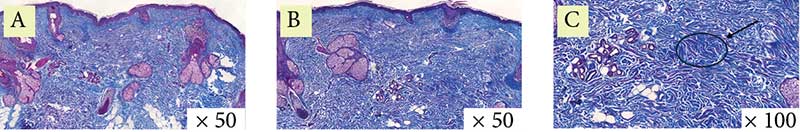

Рис. 5. Пациентка 2. Окраска по Ван-Гизону: A – до процедуры, B и C – через месяц после процедуры (стрелка указывает на участок упорядочения и структуризации коллагеновых волокон)

Рис. 6. Пациентка 2. Окраска по Массону: A – до процедуры, B и C – через месяц после процедуры (стрелка указывает на участок упорядочения и структуризации коллагеновых волокон)

Гистологически в эпидермисе отмечается уменьшение гиперкератоза, сглаживание эпидермальных гребней. В сосочковом и сетчатом слоях дермы наблюдаются единичные слабовыраженные лимфоцитарные инфильтраты, что свидетельствует о завершении воспаления, также визуализируются локальное увеличение количества коллагеновых волокон и их упорядочение (рис. 4–6).